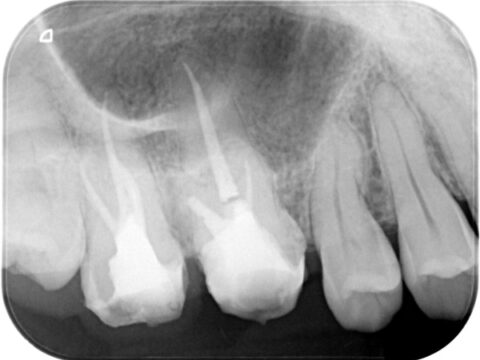

260226-001c